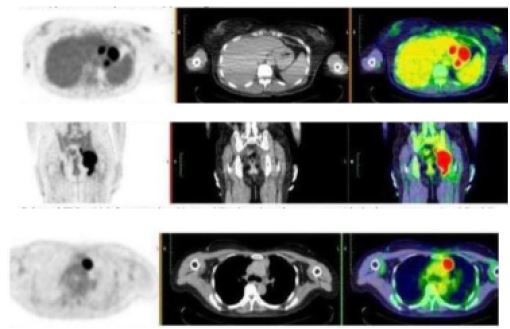

A Positron Emission Tomography (PET) CT was also performed for staging and further work-up, showing the following hypermetabolic lesions: enlarged pre-vascular lymph node, diffuse enhancing gastric wall thickening, enlarged perigastric lymph nodes, lobulated enhancing left pelvic side wall mass with erosive changes in the adjacent left ischium and acetabulum, enlarged left external and internal iliac lymph nodes and enlarged lymph node between the left pectineus and adductor muscles (Figure 5).

Image is Not Display Check it

Figure 5: PET CT scan showing hypermetabolic lesions.

During the fourth month follow-up, no recurrence of the hyper metabolic lesions was observed as seen on the repeat PET CT scan (Figure 6) showing complete metabolic response with no hyper metabolic nodal disease and interval disappearance of the enlarged lymph nodes/mass in the chest, abdomen and pelvis. There was interval resolution of the diffuse enhancing gastric wall thickening showing good treatment response. Until present, our patient is in complete remission.

Figure 6: PET CT scan showing complete metabolic response with no hyper metabolic nodal disease and interval disappearance of the enlarged lymph nodes/mass in the chest, abdomen and pelvis.

Whole-body FDG PET/CT (11/28/22)

- Enlarged prevascular lymph node

- Diffuse enhancing gastric wall thickening

- Enlarged perigastric lymph nodes

- Lobulated enhancing left pelvic side wall mass with erosive changes in the adjacent left ischium and acetabulum

- Enlarged left external and internal iliac lymph nodes

- Enlarged lymph node between the left pectineus and adductor muscles

Whole-body FDG PET/CT (4/14/23)

Complete metabolic response with no hypermetabolic nodal disease and interval disappearance of the enlarged lymph nodes/mass in the chest, abdomen and pelvis. Interval resolution of the diffuse enhancing gastric wall thickening. Known case of high-grade B-cell Lymphoma, s/p 6 cycles chemotherapy showing good treatment response.